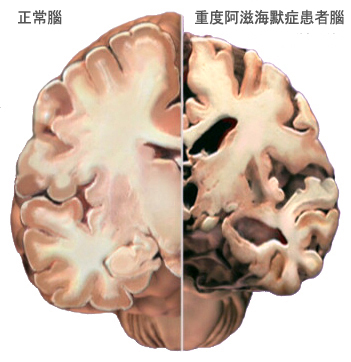

9. 重度阿滋海默症部的改變

左圖(兩耳之間的腦部橫切面圖) 左半邊是正常腦,右半邊展示出 重度患者損失大量腦細胞的情況。

• 海馬體是形成新記憶的主要地方,也是出現特別嚴重萎縮的區域。

• 腦室: 腦部充滿液體的空間將會變得更大。